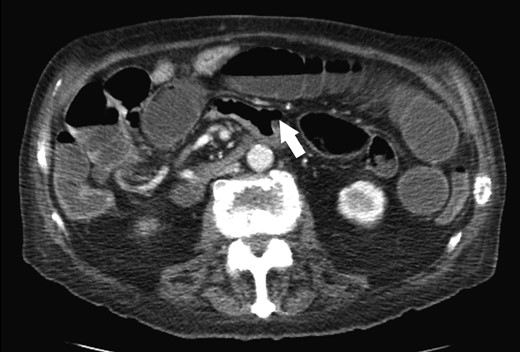

An 86-year-old male previously treated for hypertension presented to the emergency department with two days of sudden abdominal pain and nausea which resolved temporarily after self-induced emesis. Patient was examined and investigated thoroughly. Temperature was 36.3 C, blood pressure was 138/81, and pulse was 78. Physical examination revealed a tender, firm and distended abdomen with hyperactive sounds. Laboratory analysis revealed hemoglobin at 10.3 g/dL, leukocytes 3.1 K/cmm, urea nitrogen 19 mg/dl, creatinine 0.6 mg/dl, sodium 137 mmol/l, potassium 3.6 mmol/l, chloride 104 mmol/l, bicarbonate 24 mmol/l, calcium 8.6 mg/dl, total protein 6.3 g/dl, albumin 3.1 g/dl, total bilirubin 0.7 mg/dl, alkaline phosphatase 98 U/l, SGOT 20 U/l, SGPT 27 U/l. Laboratory values were consistent with patient’s previous clinic visits. Computed tomography (CT) of the abdomen revealed a fluid-filled, significantly dilated stomach as well as multiple dilated loops of small bowel with air-fluid levels consistent with mechanical small bowel obstruction caused by intussusception of small bowel (Fig. 1). After initial fluid resuscitation and antibiotic administration, consent was obtained for emergent exploratory laparotomy. The exploratory laparotomy revealed a 3.0 × 2.5 cm intraluminal calculus in the ileum responsible for the small bowel obstruction, without evidence of intussusception (Fig. 2). The obstructing enterolith was ‘milked’ proximally until it reached, and subsequently ‘fell into,’ an isolated 6.0 × 3.0 cm jejunal diverticulum which had not been previously noted on CT imaging. The enterolith was removed along with the segment of the jejunum containing the isolated diverticulum, which was the source of the enterolith (Fig. 3). On histologic examination, the mucosa of the extracted diverticulum was found to be granular and erythematous; the remaining small bowel had marked mucosal ulceration and near-transmural inflammation with granulation tissue. Hospital course was complicated by decreased urine output that resolved after fluid resuscitation. On the fourth postoperative day, nasogastric tube was discontinued, diet was advanced and tolerated, and the patient was discharged. Review of the patient’s CT scan of the abdomen revealed the isolated jejunal diverticulum that was consistent with the excised diverticulum (Fig. 4).

Enterolith-induced small bowel obstruction resembling intussusception (white arrow).